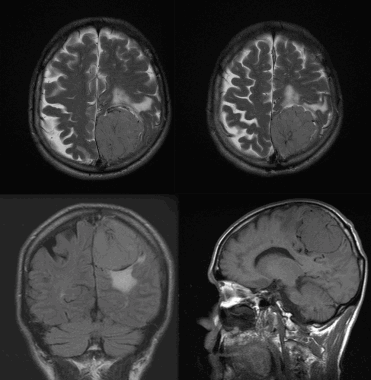

(Слева) МРТ, Т2-ВИ, корональный срез: у мужчины 47 лет определяется внемозговое образование однородной структуры с четкими контурами с минимальным отеком.

(Справа) МРТ, постконтрастное Т1 -ВИ, аксиальный срез: у этого же пациента визуализируется интенсивное относительно однородное контрастное усиление. Обратите внимание на компрессию треугольника левого бокового желудочка. Несмотря на отсутствие агрессивных рентгенологических признаков при хирургической резекции и гистологическом исследовании была диагностирована злокачественная Менингиома grade III. Для окончательного установления гистологического типа и степени злокачественности менингиомы необходима биопсия.